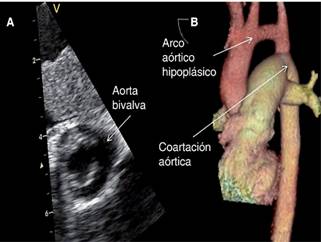

Paciente femenina de 21 años, de medio socioeconómico medio-bajo, con antecedentes de dificultad para subir de peso desde la infancia y cuadros de vías respiratorias muy frecuentes (al menos cinco a seis por año) caracterizadas por tos no productiva y fatiga, relata que durante sus años escolares no podía efectuar ejercicios ni deporte al igual que sus compañeros por disnea. Menarca a los 16 años, con ritmo irregular y núbil, al interrogatorio dirigido mencionó disnea de medianos esfuerzos de seis meses de evolución, consultó a facultativo quien diagnosticó estenosis mitral de origen reumático, le prescribió diurético mostrando mejoría. Acudió a urgencias por sufrir de inicio súbito: disnea a pequeños esfuerzos, diaforesis y sensación de palpitaciones. A la exploración: paciente angustiada, peso 39 kilogramos, talla 150 cm, IMC de 17.3 y en área torácica el ápex se encontró en el sexto espacio intercostal izquierdo sobre la línea axilar anterior. A la auscultación: soplo expulsivo aórtico grado IV/IV trasmitido a ambas carótidas; el primer ruido bajo en tono con soplo mesodiastólico grado III/IV. Abdomen normal, edema discreto en extremidades por debajo de rodilla con Godet +; no se detectaron pulsos arteriales en extremidades pélvicas estando presentes en las torácicas con 140 lpm. La tensión arterial en extremidad torácica superior derecha en 90/60 y los campos pulmonares con estertores crepitantes generalizados. Oximetría de pulso en mano derecha en 85% con aire ambiental que mejora a 94 con puntas de oxígeno a 3 L/min. Con impresión diagnóstica de coartación aórtica y lesión de válvula mitral se efectuó electrocardiograma, el cual reveló: taquicardia supraventricular de 240 lpm y vía accesoria oculta sugestiva de localización posteroseptal izquierda con conducción retrógrada (Figura 1A). Se administró amiodarona y cardioversión eléctrica, obteniendo ritmo sinusal con frecuencia cardiaca 66 lpm, AQRS en cuadrante superior derecho, QRS ensanchado por bloqueo de rama derecha, PR menor de 0.12 seg. y presencia de ondas delta (Figura 1B).

Figura 1: Electrocardiograma que muestra en A. Taquicardia supraventricular de 240 lpm y vía accesoria oculta sugestiva de localización posteroseptal izquierda con conducción retrógrada. En B. Posterior a amiodarona y cardioversión eléctrica obteniendo: ritmo sinusal con frecuencia cardiaca 66 lpm, AQRS en cuadrante superior derecho, bloqueo de rama derecha, PR menor de 0.12 seg. y presencia de ondas delta.